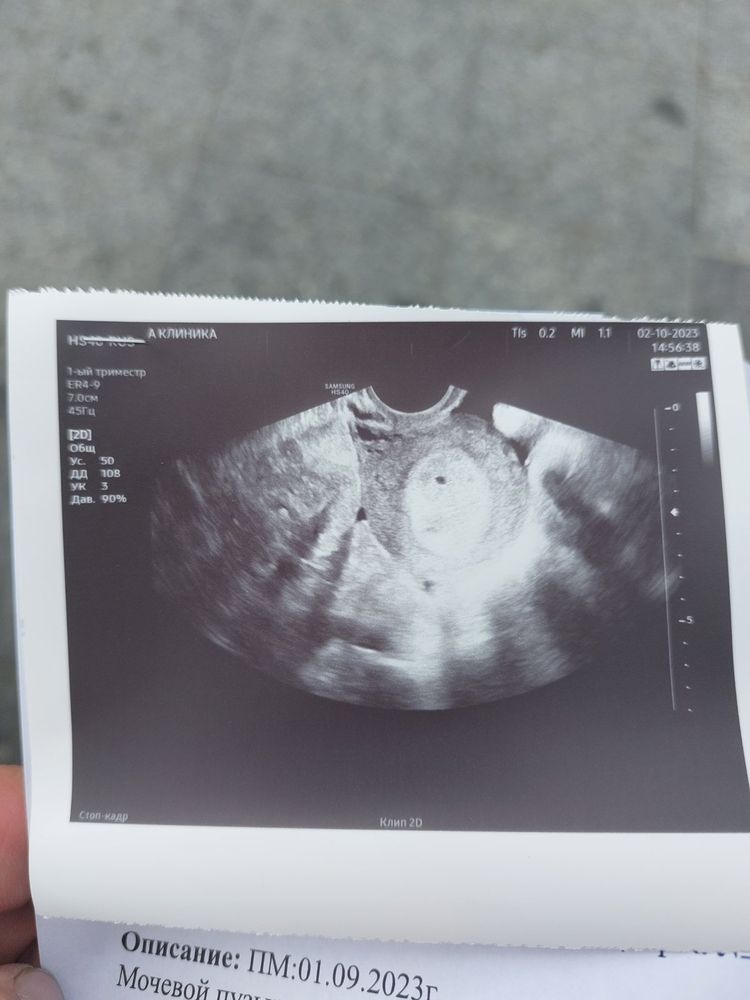

Kukla . kom в Здоровье будущей мамы 2 года Беременность узи Результаты: УЗИ, КТГ, доплера, скрининга Как вам узи нормально или надо ждать и на следующее идти Посмотрите еще 20 записей на эту тему Отменить Ответить Nastasya Конечно, ждать и идти опять. Беременность не подтверждена даже ещё, стоит под вопросом. Подождите недельку 03.10.2023 Ответить Kukla . kom Nastasya , а что вы по фото узи Скажите 03.10.2023 Ответить Nastasya Kukla . kom, я не врач🤷♀️. Сходите через пару-тройку дней, вам уже точно скажут 03.10.2023 Ответить Kukla . kom Nastasya , спасибо 03.10.2023 Ответить Беременность нормально ли это Помогите с узи Чаты Беременных Выберите чат: Январята-2026 Февралята-2026 Мартята-2026 Апрелята-2026 Майчата-2026 Июнята-2026 Июлята-2026 Августята-2026